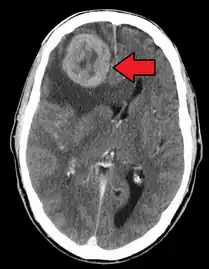

Illustration showing hematogenous metastasis

Some cancer cells known as circulating tumor cells acquire the ability to penetrate the walls of lymphatic or blood vessels, after which they are able to circulate through the bloodstream to other sites and tissues in the body.[6] This process is known (respectively) as lymphatic or hematogenous spread. After the tumor cells come to rest at another site, they re-penetrate the vessel or walls and continue to multiply, eventually forming another clinically detectable tumor. This new tumor is known as a metastatic (or secondary) tumor. Metastasis is one of the hallmarks of cancer, distinguishing it from benign tumors.[7] Most cancers can metastasize, although in varying degrees. Basal cell carcinoma for example rarely metastasizes.[7]